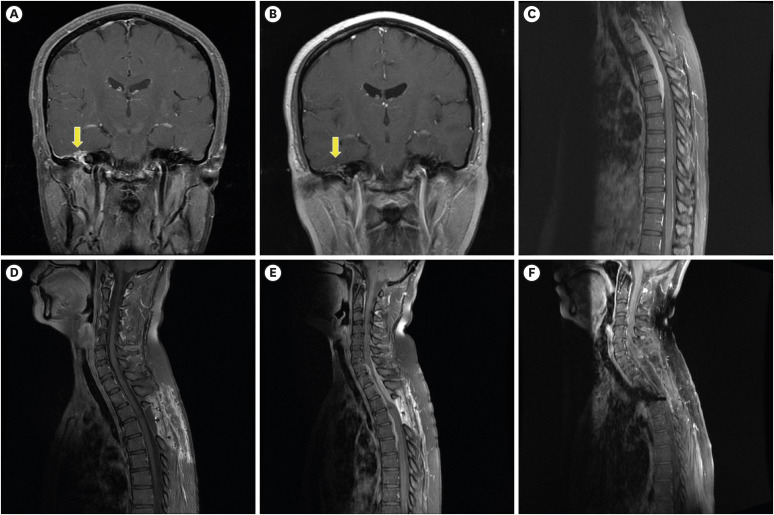

这个病例报告描述了一个罕见的抗中性粒细胞细胞质抗体相关的肥厚性厚性脑膜炎在一个49岁的女性颅脑和脊柱病变。最初的治疗包括减压椎板切除术和类固醇治疗,随后在症状复发后增加免疫抑制剂治疗。经过10年的随访,患者症状明显改善,运动功能恢复。这个病例强调了早期诊断、多学科方法和综合药物治疗在治疗这种罕见疾病中的关键作用。

This case report describes a rare presentation of antineutrophil cytoplasmic antibodies-associated hypertrophic pachymeningitis in a 49-year-old woman with cranial and spinal lesions. Initial management comprised decompressive laminectomy and steroid therapy, with the subsequent addition of immunosuppressant therapy following symptom recurrence. After a ten-year follow-up, significant symptom improvement and return of motor function were noted. This case emphasizes the crucial role of early diagnosis, a multidisciplinary approach, and combined medical therapy in managing this rare condition.